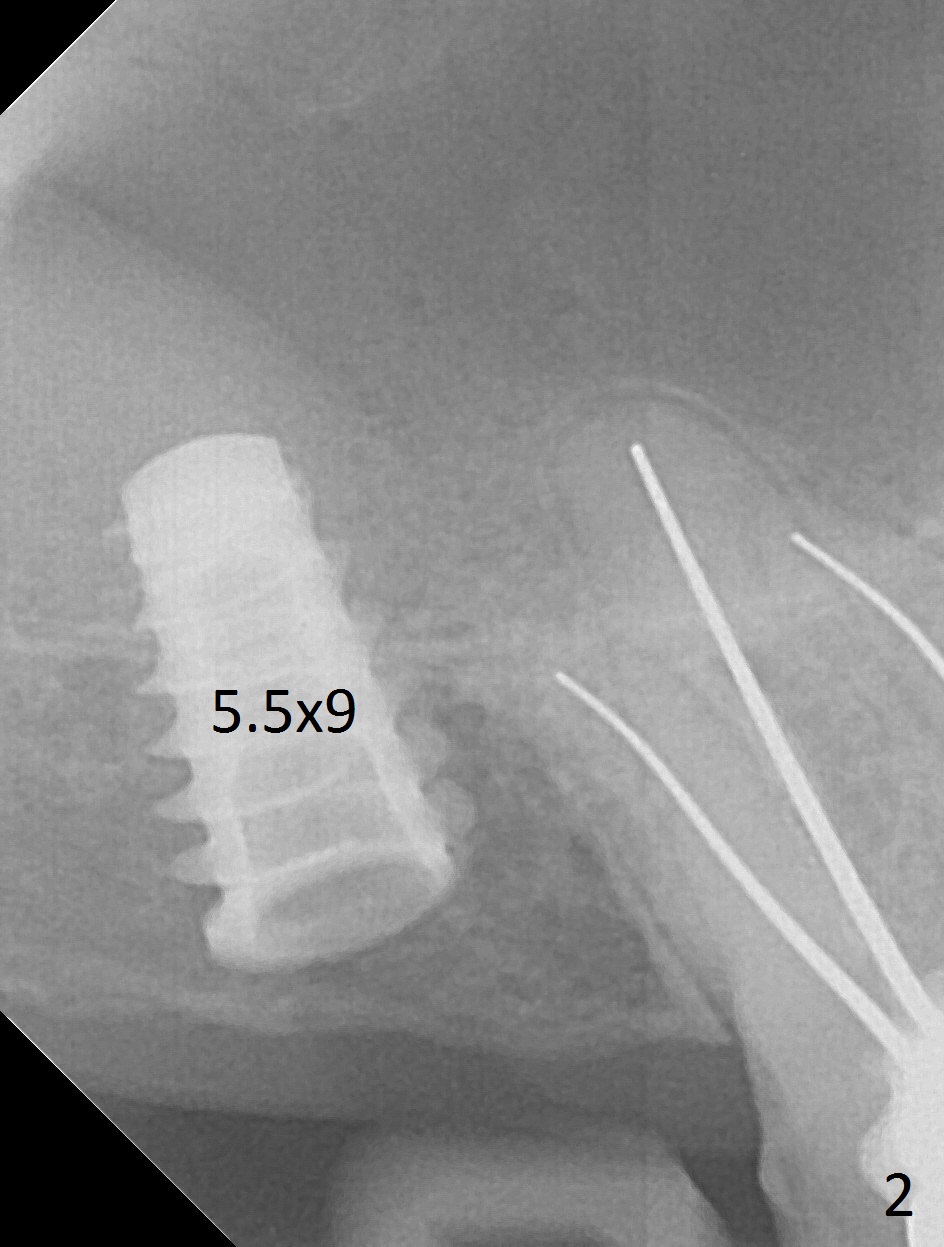

Since the ridge is wide at the site of #2, Magic Split is used for access (flapless) and bone expansion. The bone is so soft that there is no resistance until 4.3 mm Magic Expander is used for 9 mm (Fig.6). A 5 mm tap drill is stable (Fig.1), so are a 5.5x9 mm dummy implant (Fig.2) and a 6x9 mm IBS implant (Fig.3 (<: sinus lift)). In fact the distal thread is still supracrestal (Fig.4 (BW)). After additional 2 mm placement, the distal thread is subcrestal (Fig.5); the mesial margin of a 6.5x4(4) mm abutment is subgingival. A longer cuff (5 mm instead of 4 mm) is more favorable for future restoration. At present the abutment (Fig.7) as well as the tooth #3 with rugged surfaces is used to hold periodontal dressing in place. The abutment margin is completely subgingival 3 months postop (Fig.8 (white dashed line: gingival margin)). It appears that the implant is placed ~ 1 mm deeper than ideal (Fig.9). Diode laser is used for gingivectomy prior to impression. The abutment screw becomes loose 2 months post cementation. After retightening, occlusal equilibrium is conducted with 3 layers of articulating paper. Night guard is provided. The crown/abutment dislodges 1 year 2 months later. Since the gingiva is erythematous, a 6x7 mm healing abutment is placed (Fig.10). The implant seems to have been placed too deep and palatal. It appears that an abutment driver should be buried to prevent the screw re-loosening. Guided surgery should have been done.